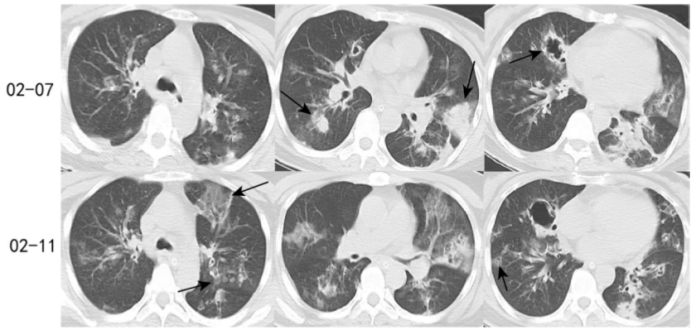

第2天(2月7日),患者病情进展迅速,嗜睡状态,呼吸困难明显加重,氧饱和度难以维持,复查血气示:pH 7.094,PaO2 69.8 mmHg,PaCO2 104 mmHg,予气管插管呼吸机辅助通气。完善检查示:痰呼吸道病原体分子检测(-);甲流+乙流病毒核酸检测(-);呼吸道病毒抗原检测(-);优生八项TORCH测定:巨细胞病毒IgG抗体、单纯疱疹Ⅰ型病毒IgG抗体(+);痰细菌+真菌培养(-);T-SPOT(-);血G+GM试验(-);胸部CT示:两肺多发高密度,部分伴空洞形成,考虑感染性病变。2月11日胸部CT可见磨玻璃浸润影较前进展,局部气管壁增厚及树芽征(图1)

图1  胸部CT图像(2月7日,2月11日)

注:可见两肺多发高密度,箭头所示结节周围伴磨玻璃影,空洞形成。

第6天(2月11日),患者憋喘未见明显改善,呼吸机参数下调困难。加用两性霉素B(首日5 mg qd,每日增加5 mg)。复查胸部CT示:多发斑片状高密度影,部分病灶内见空洞影,较2月7日片有所进展。完善床边气管镜示:镜下可见气道黏膜充血、水肿、糜烂,行镜下支气管肺泡灌洗,灌洗液送G+GM试验,未外送NGS。

本例患者胸部CT可见两肺多发高密度,结节周围伴磨玻璃影晕征,空洞形成;随着病情进展,磨玻璃浸润影增多,局部气管壁增厚、出现树芽征等。